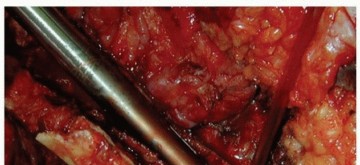

تُعرف جراحة مراجعة مفصل الورك بأنها إجراء جراحي يتم فيه استبدال أحد مكونات مفصل الورك الصناعي أو كلاهما (الدعامة الفخذية أو مكون الحُق) بسبب فشل الزرع الأصلي. على الرغم من النجاح الساحق والموثوقية طويلة الأمد لاستبدال مفصل الورك الكلي الأولي، إلا أن هناك عدة أسباب قد تستدعي إجراء جراحة مراجعة.

تُعد الدعامات الفخذية الأسطوانية غير الأسمنتية المطلية بالمسام بشكل كامل خيارًا علاجيًا متقدمًا وحلاً فعالاً في العديد من حالات مراجعة مفصل الورك. تعتمد هذه الدعامات على تصميم فريد يسمح بنمو العظم داخل سطحها المسامي، مما يوفر تثبيتًا بيولوجيًا قويًا ومستقرًا على المدى الطويل. يعتبر الأستاذ الدكتور محمد هطيف في صنعاء مرجعًا في استخدام هذه التقنية، ملتزمًا بتقديم أحدث وأنجح العلاجات لمرضاه.

على الرغم من ندرتها، يمكن أن تحدث العدوى حول المفصل الصناعي بعد فترة طويلة من الجراحة الأولية، مما يستدعي إزالة المكونات المصابة وتنظيف المنطقة، ثم إعادة زرع مكونات جديدة.